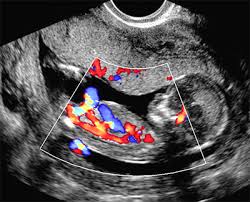

Ultrassonografia Obstétrica com Doppler A ultrassonografia com Doppler é essencial para avaliar o fluxo sanguíneo na placenta e no bebê, garantindo que tudo esteja dentro dos parâmetros normais.

✅ Monitora a oxigenação e nutrição do feto.

✅ Detecta possíveis complicações, como restrição de crescimento intrauterino (RCIU).

✅ Auxilia no diagnóstico de pré-eclâmpsia e insuficiência placentária.

Esse exame é fundamental para um acompanhamento seguro da gestação!